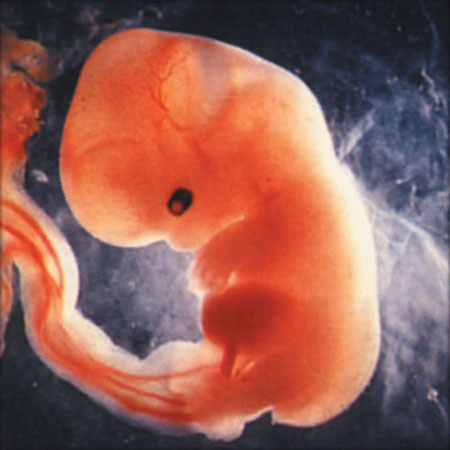

05 недеља

06 недеља

од зачећа 9 недеља